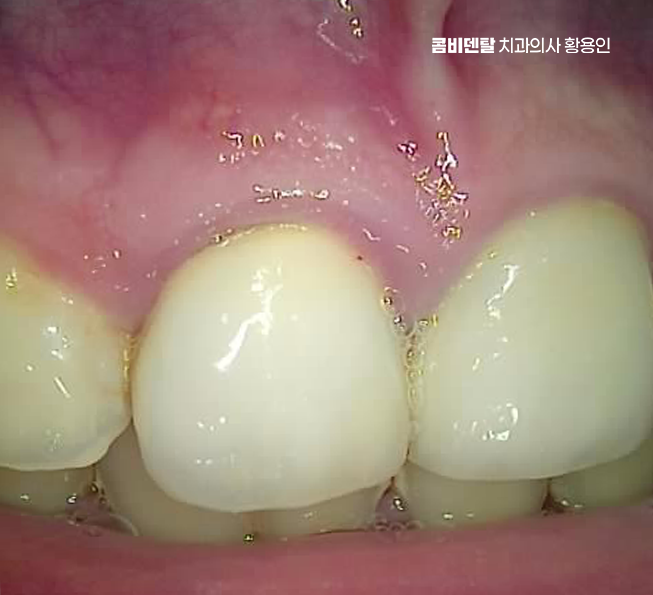

앞니는 웃을 때, 말할 때 먼저 보이는 자리여서 과거에는 심미성만 우선해서 치료를 하거나, 그 당시 기술로 가능한 선에서만 보철을 해둔 경우가 많은데 시간이 지나면 잇몸이 내려가면서 보철물 가장자리가 드러나거나 회색 선이 드러나는 경우나 2차 충치 등의 문제가 나타날 수 있었어요

신경치료가 끝나면 그 다음은 크라운 치료로 이어지게 되는데 앞니는 어금니와 다르게 보이는 게 중요해서 크라운 선택 시엔 재료가 중요해서 올세라믹 크라운이 주로 쓰이고 내구성이 좀더 중요한 경우에는 지르코니아 크라운도 많이 쓰이고 있으며 앞니 치료 시에는 자연치처럼 투명도와 색감이 중요하고 특히 빛 반사까지도 고려해야 하므로 앞니 신경치료 크라운 종류의 선택이 중요할 수 있었어요

앞니 신경치료 크라운의 경우 심미성과 기능을 동시에 만족시켜야 하기 때문에 치료 계획도 섬세하게 세워야 하는데 색조 선택도 중요하고, 인접 치아와 조화를 이루는 형태, 길이, 각도까지 전부 신경 써야 하기 때문에 경험 많은 치과의사와 잘 상의하는 것이 필요할 수 있어요